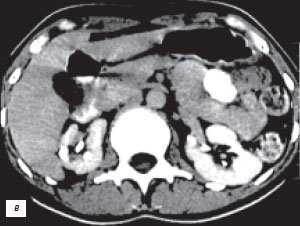

в) КТ с контрастным усилением.

е) КТ с контрастным усилением.

Многолетний опыт экскреторной урографии показал, что чашечно-лоханочные системы имеют крайне большое количество вариантов строения. Они практически индивидуальны не только для каждого человека, но и для левой и правой почек у одного субъекта. С развитием и все более широким использованием УЗИ и РКТ, позволяющим прослеживать как внутренние, так и наружные контуры паренхимы почек, на наш взгляд, аналогичное положение складывается и в отношении вариантов анатомического строения паренхимы почек. Сопоставление эхо- и компьютерно-томографических данных с урографическими при различных вариантах псевдоопухолей почек показало, что между анатомическим строением паренхимы и чашечно-лоханочных систем почек имеется взаимосвязь. Она выражается в конгруэнтности медиального контура паренхимы в эхо- или компьютерно-томографическом изображении с латеральным контуром чашечно-лоханочных систем, условно проведенным на экскреторных урограммах или на компьютерных томограммах с контрастным усилением [4, 17, 18]. Этот симптом прослеживается при обычном строении паренхимы и чашечно-лоханочных систем, а также при "перемычке" паренхимы почки, предсталяющей собой вариант анатомического строения. При опухоли почки, являющейся приобретенным патологическим процессом, конгруэнтность контуров паренхимы и чашечно-лоханочных систем почек нарушается (рис. 4).

Рис. 4. Симптом конгруэнтности контуров паренхимы и чашечно-лоханочной системы почки при неполной "перемычке" паренхимы (объяснение в тексте).